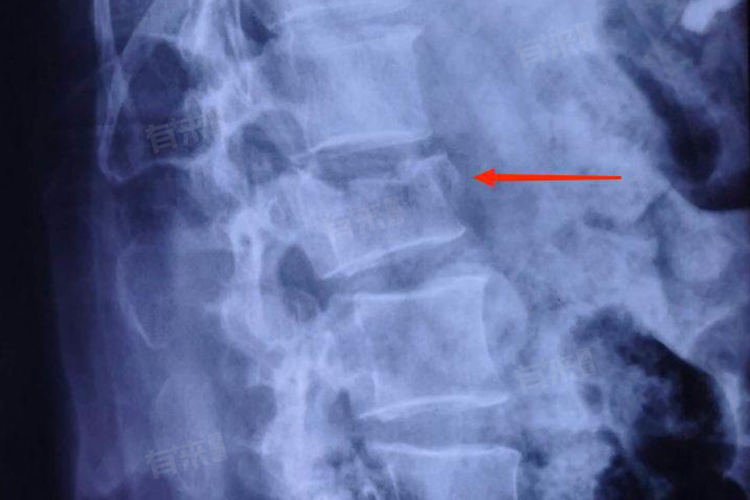

腰2压缩性骨折的恢复时间因骨折严重程度和体质因素而异,一般来说,轻度骨折可能需要3个月左右恢复,严重的则可能需要4-6个月甚至更长时间。

- 如果是轻度的腰2压缩性骨折,椎体压缩程度不超过三分之一,通常采取保守治疗。患者需要严格卧床休息一段时间,一般为6-8周。在此期间,可配合药物治疗缓解疼痛和促进骨折愈合。之后可以在支具保护下逐渐下地活动,经过一段时间的康复训练,大约3个月左右可基本恢复正常生活。

- 当椎体压缩程度在三分之一到二分之一之间时,恢复时间会相对延长。除了保守治疗的措施外,可能需要进行物理治疗来促进局部血液循环和肌肉功能恢复。这个阶段的患者可能需要卧床8-12周,然后在医生指导下进行康复训练,大约4-6个月才能逐渐恢复正常活动。

- 如果腰2椎体压缩程度超过二分之一,或者伴有神经损伤等情况,往往需要手术治疗。手术后患者仍需卧床一段时间,一般为2到3个月。随后进行康复治疗,包括物理治疗、康复训练等。整个恢复过程可能需要半年以上,甚至更长时间,且可能会遗留一些后遗症。